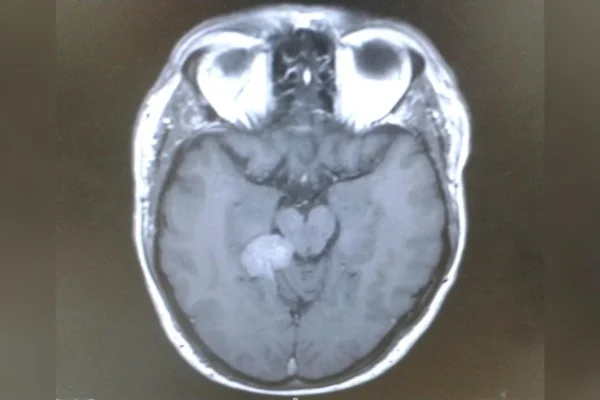

Homem descobre tumor cerebral após ficar 2 anos ouvindo zumbidos Ouvir 19 de dezembro de 2025 Tumores cerebrais costumam se desenvolver de forma silenciosa, sem sintomas claros nas fases iniciais. Em muitos casos, os sinais aparecem de forma pouco específica e podem ser confundidos com problemas rotineiros. Para Darren Harris, britânico de 59 anos, o único alerta por quase dois anos foi um zumbido constante no ouvido. Morador de Paignton, no sul da Inglaterra, Darren conviveu com o incômodo sem imaginar que o som persistente estava ligado a algo mais sério. O zumbido, conhecido clinicamente como tinnitus, é relativamente comum e pode ter diversas causas. Diagnostico do tumor cerebral Após relatar o zumbido a médicos, Darren foi encaminhado para um teste auditivo de rotina. Alguns tratamentos chegaram a aliviar o desconforto, mas os profissionais decidiram investigar mais a fundo. Exames de imagem foram solicitados em sequência, o que aumentou a apreensão do paciente. “Eu sabia que algo estava errado, mas ninguém conseguia me dizer o que. A equipe da ressonância magnética não pode discutir os resultados, então a cada consulta eu saía frustrado e preocupado”, contou ele ao site do Brain Tumour Research. A confirmação veio em março de 2015. Após ser encaminhado a um neurocirurgião, Darren recebeu o diagnóstico de um meningioma tentorial em estágio inicial. Trata-se de um tumor geralmente benigno e de crescimento lento, que se desenvolve a partir das meninges, as membranas que envolvem o cérebro. No caso dele, a lesão estava localizada na base do cérebro, em uma área considerada inoperável por causa dos riscos do procedimento. Leia também Saúde Neurologista explica sintomas comuns que podem indicar tumor cerebral Saúde Visão dupla em voo leva jovem de 24 anos a descobrir tumor cerebral Saúde Menino de 6 anos morre após tumor cerebral ser confundido com cansaço Saúde Com dor de cabeça frequente, mulher descobre tumor cerebral de 15 anos Apesar de não ser canceroso, esse tipo de lesão pode causar uma série de sintomas ao pressionar estruturas cerebrais e nervos. Entre eles estão zumbido no ouvido, dores de cabeça, alterações na visão, perda auditiva, diminuição do olfato e dificuldade para engolir. Se não tratado, pode se tornar potencialmente fatal. Tratamento Sem a possibilidade de cirurgia convencional, Darren recebeu a opção de se submeter à radiocirurgia com Gamma Knife, uma técnica avançada que utiliza centenas de feixes de radiação concentrados para destruir células tumorais com precisão milimétrica, preservando o tecido saudável ao redor. “Eles fixaram uma estrutura metálica no meu crânio para me manter imóvel, mapearam o tumor em três dimensões e atingiram exatamente o ponto necessário”, conta Darren, que é analista funcional de TI. O tratamento custou cerca de 35 mil libras, o equivalente a aproximadamente 220 mil reais. Darren conseguiu realizar o procedimento graças a um plano de saúde privado, mas destaca que muitas famílias não teriam condições de arcar com esse tipo de custo. 2 imagensFechar modal.1 de 2 O meningioma é um tumor geralmente benigno, de crescimento lento, que se forma a partir das meninges, as membranas que envolvem o cérebro Divulgação/Brain Tumour Research 2 de 2 A confirmação veio em março de 2015, quando ele foi encaminhado a um neurocirurgião Divulgação/Brain Tumour Research Embora o tratamento tenha sido bem-sucedido no controle do tumor, Darren passou a lidar com novos desafios de saúde. Ele desenvolveu epilepsia e foi diagnosticado com fibrilação atrial, uma arritmia cardíaca associada ao estresse causado pelas convulsões. Desde então, precisou passar por diferentes procedimentos cardíacos e convive com efeitos neurológicos permanentes, como alterações visuais e formigamento no lado esquerdo do corpo. Ainda assim, considera-se um sobrevivente. “Completar dez anos desde o diagnóstico nunca foi algo garantido para mim. Sei o quanto sou sortudo por ainda estar aqui, graças aos tratamentos e ao conhecimento disponíveis hoje”, afirma. Para ele, a experiência reforçou a importância do investimento contínuo em pesquisa. Darren acredita que histórias como a dele mostram como sintomas aparentemente simples não devem ser ignorados e como o avanço da medicina pode mudar trajetórias que, à primeira vista, pareciam sem saída. “Nem todos têm a mesma chance. Por isso, apoiar a pesquisa é essencial para que mais pessoas tenham acesso a diagnósticos precoces, tratamentos eficazes e, no futuro, à cura”, conclui. Notícias